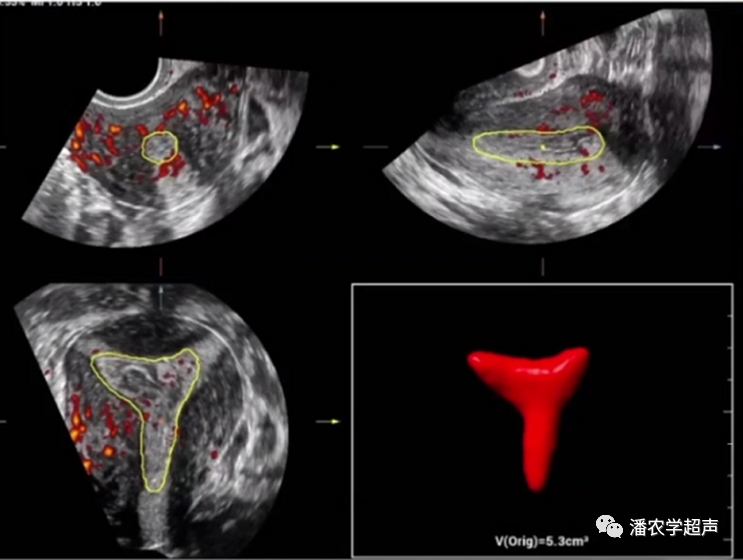

腔内三维超声评估子宫内膜容受性

•腔内三维超声技术具有无创方便,可重复性,实时监测,可预测性。

超声参数目前是临床评估围着床期子宫内膜接受胚胎着床能力的主要参考

•3D技术同时评估子宫形态、宫腔容积(宫腔面积、内膜容积)、内膜厚度和类型等【遵循子宫形态学超声评估(MUSA)专家共识】,方法准确客观;内膜血流、血管血流及指数取决于仪器性能。

•三维容积超声显示子宫内膜容积<2cm³时,妊娠率和种植率显著降低;妊娠需要的内膜容积最小值2cm³;体外受精(In Vitro Fertilization, IVF)和胚胎移植(embryotransfer,ET)日内膜容积<2.5cm³被界定为低容量,与较差的妊娠结局相关。移植日内膜容积<2.5cm³时妊娠率明显低于内膜容积≥2.5cm³。内膜容积<2.5cm³对容受性阴性预测价值较强;>2~3.5cm³妊娠率明显增加,但上限未知。